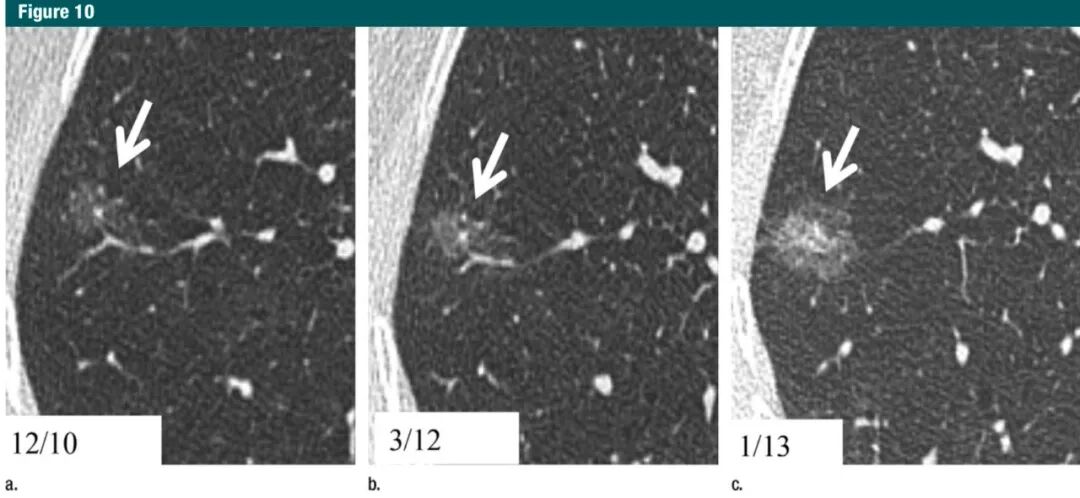

目前,大量文献研究结果显示≥6mm的纯磨玻璃结节随访5年是安全的,通常经过3-4年即可确诊该结节是否增大,仅有少数病例发展诊断为浸润性癌(图9,10)。

图10:a.右中肺1mmCT横断面扫描,显示一个10mm纯磨玻璃结节(箭头);b:在同一CT层面,15个月后随访,结节的密度有非常轻微的增高;c:在同一CT层面,10个月后二次随访,显示结节进展为更大的部分实性结节;术后病理为IA期浸润性腺癌(鳞屑样生长为主型)7Gc帝国网站管理系统

7Gc帝国网站管理系统